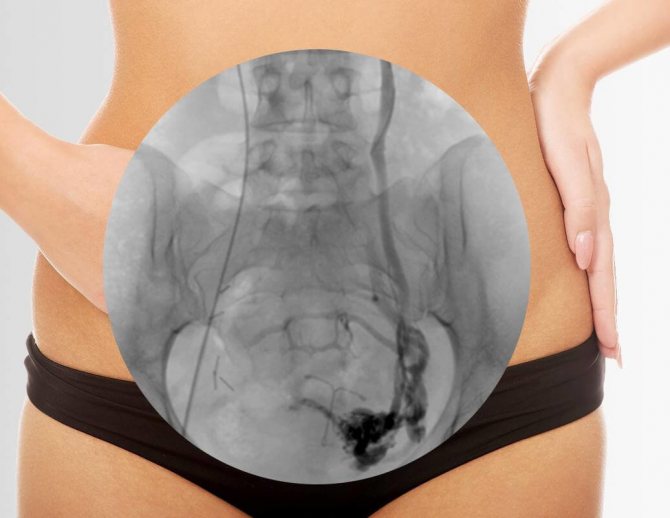

- Флебография – инвазивное исследование, которое позволяет с высокой точностью определить наличие и степень заболевания;

- Селективная овариография – изучение состояния вен с помощью введения контрастного вещества, считается самым объективным диагностическим методом.

- Избирательная оварикография. Красящим веществом производят контрастирование интересуемой вены, после чего делают снимки, с помощью которых оценивается ход сосудов, их стенки, а также степень нарушения кровотока.

Еще одним информационным методом диагностики является флебография. Способ основан на получении рентгеновских снимков всей кровеносной сети малого таза. Процедура проходит в несколько этапов. Сначала через ключичную или бедренную вену вводят длинный очень тонкий катетер, который продвигается вплоть до центральных вен малого таза.